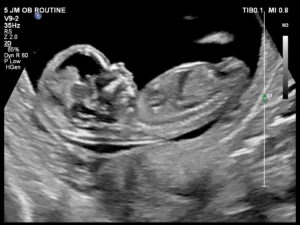

Ultrasound